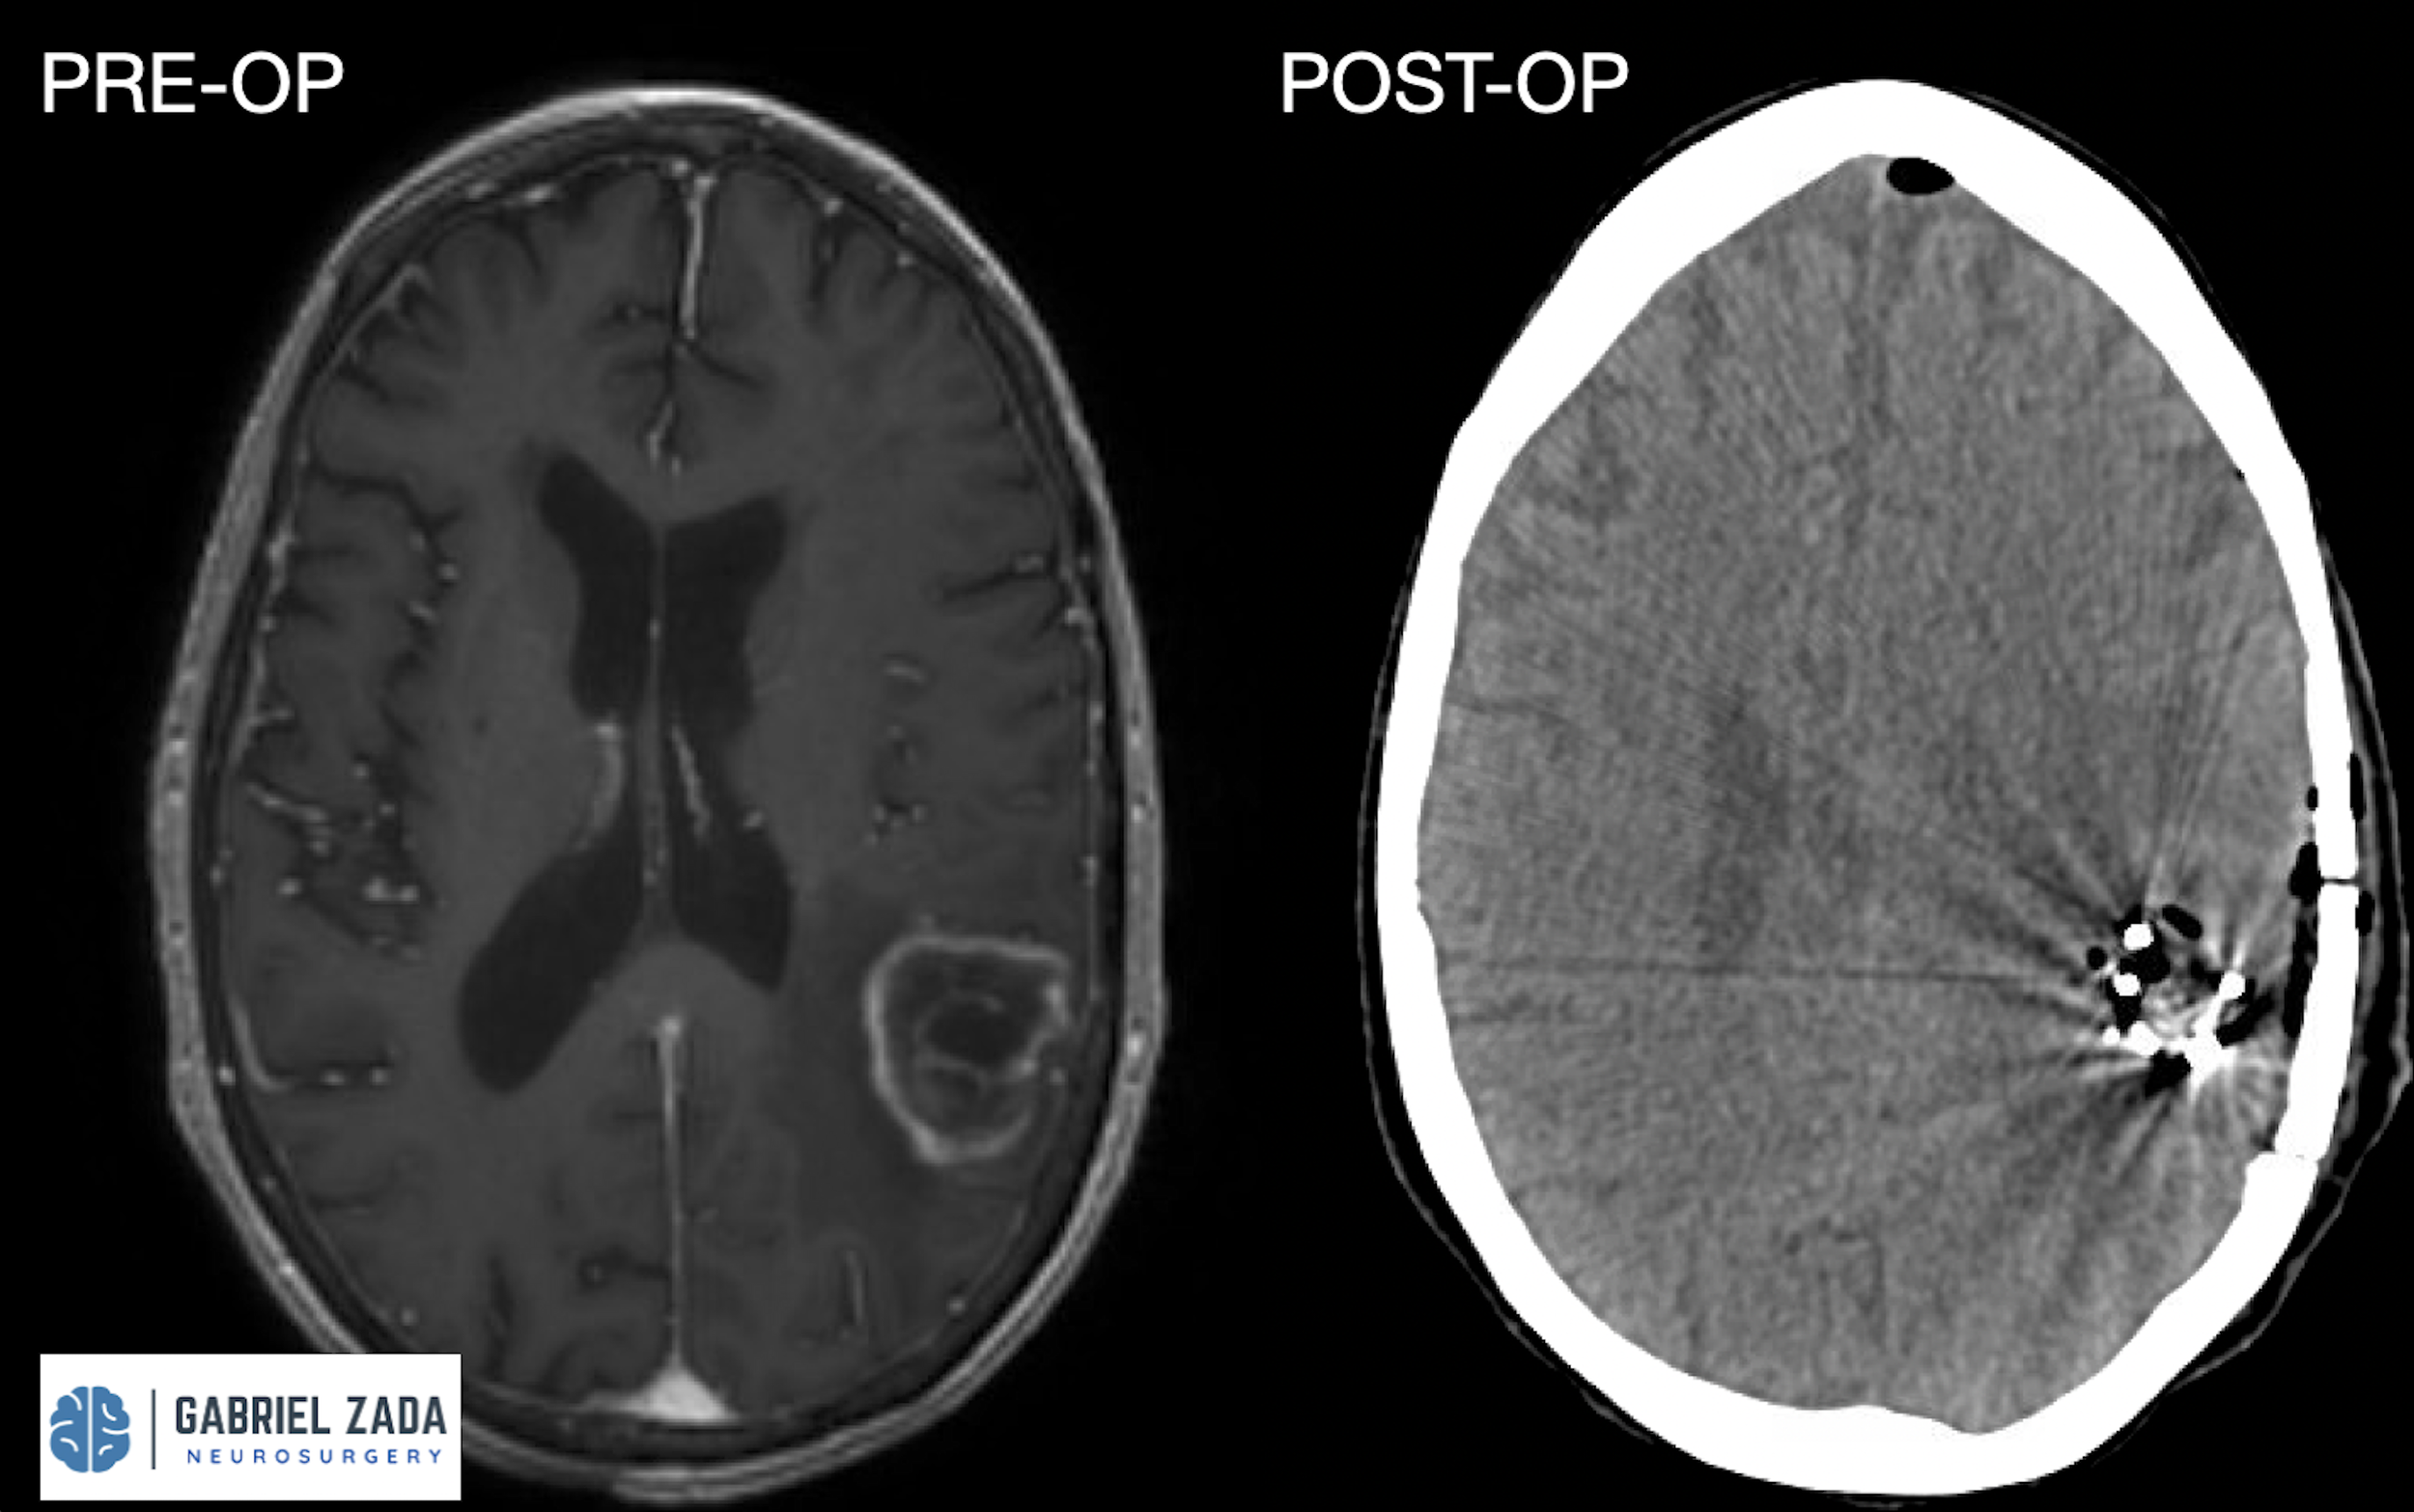

Explore this comprehensive gallery featuring pre‑ and post‑operative imaging of patients with skull‑base tumors treated by Gabriel Zada, MD, MS, FAANS, FACS. These cases highlight Dr. Zada’s expertise in advanced neurosurgical techniques and outcomes.

*Representative cases shown for educational purposes. All images de-identified. Individual results vary.